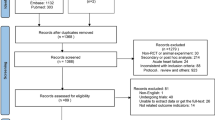

The TEHAF study, a randomised controlled trial performed between 2007 and 2010, compared tailored telemonitoring using the Health Buddy to usual care in HF patients [10]. Further study details have been published elsewhere [7]. In brief, HF patients with New York Heart Association (NYHA) functional class 2–4 that were treated by a cardiologist and were in the care of a heart failure nurse (HFN) were included. HF was defined as ‘at least one episode of fluid retention requiring diuretics, either with an echocardiographic left ventricular ejection fraction ≤40% or a preserved ejection fraction with diastolic dysfunction’ [7]. Patients were included in the study either during a visit to the outpatient clinic of one of the participating centres (Sittard, Heerlen, Maastricht) or when they were visited by a HFN, in the home situation. Exclusion criteria were: unable to give informed consent, visual impairment, hearing impairment in combination with living alone, no command of the Dutch language, planned hospital admission within 3 months and/or chronic obstructive pulmonary disease, Parkinson’s disease, extracorporeal dialysis, (pre)dementia or another disease with an expected shortened lifespan. A total of 382 patients were included. The trial was completed by 301 patients (79%). All patients who did not finish the study were excluded from all further analyses. The follow-up period was 12 months. Before randomisation, written informed consent was obtained. Randomisation was computer-generated with stratification per centre. Four times during the study, data on patients’ self-care behaviour (measured with the European Heart Failure Self-Care Behaviour Scale) [11], self-efficacy (measured with the Barnason Efficacy Expectation Scale) [12] and compliance (measured with the Heart Failure Compliance Scale) [13] were collected (Fig. 1).